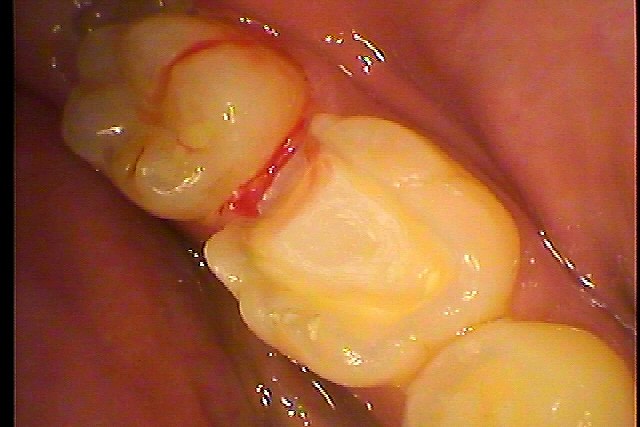

この中央の歯が痛むとのこと

一見何もないように見えますが、、、

中央から遠心部にかけてCR樹脂がしてあり、黒く感じます

少し削っていくと、、、